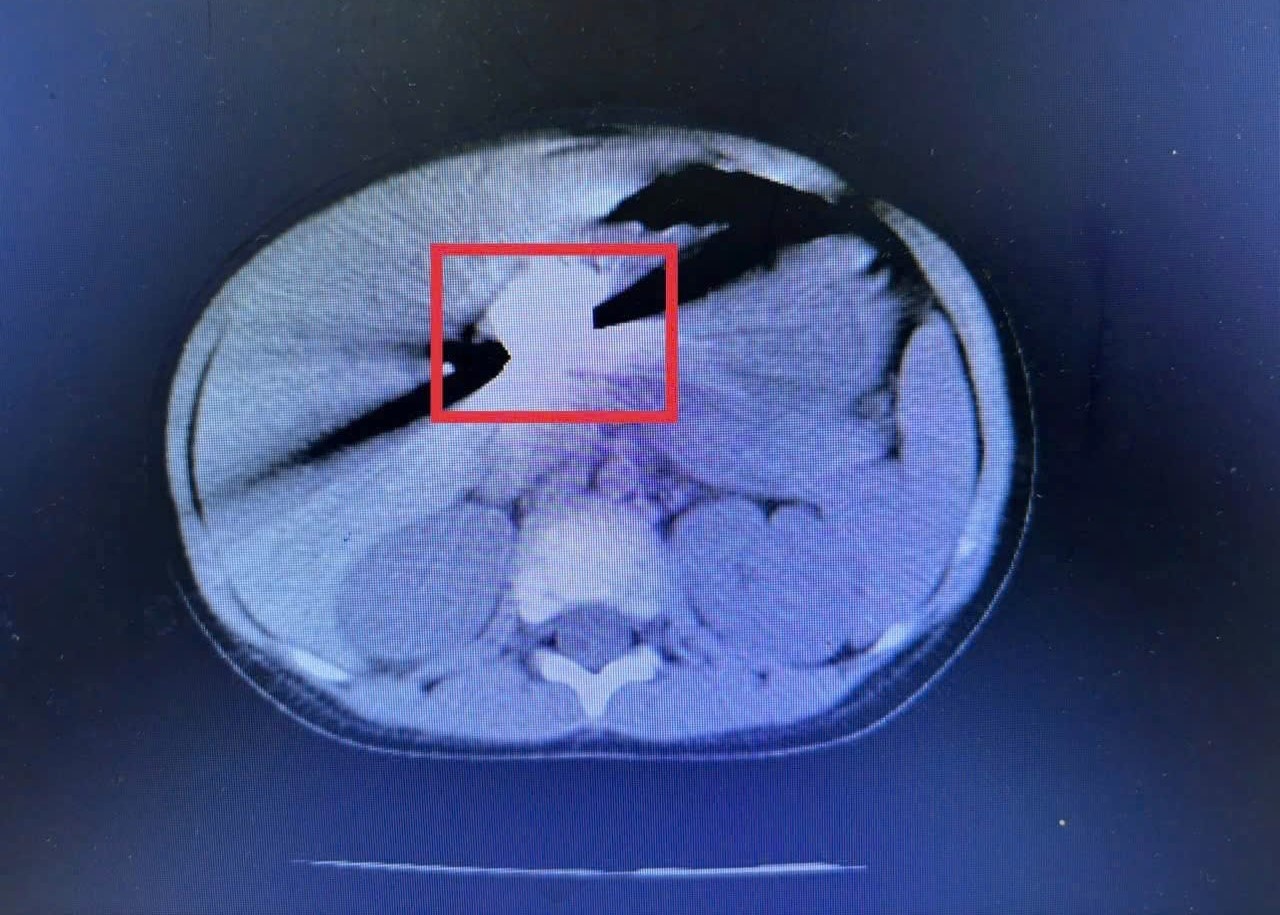

Một trường hợp điển hình là bé 3 tuổi ở xã Khánh Vĩnh, nhập viện đêm 25/11/2025 trong tình trạng quấy khóc nhiều. Gia đình cho biết buổi sáng cùng ngày bé vô tình nuốt phải đồng xu khi đang chơi. Kết quả chụp CT phát hiện dị vật nằm trong dạ dày. Các bác sĩ đã nhanh chóng tiến hành nội soi và lấy ra đồng xu vào rạng sáng 26/11/2025. Bé hồi phục tốt và được xuất viện hôm sau. Trẻ từ 1 đến 5 tuổi thường có thói quen cho đồ vật vào miệng để khám phá. Vật nhỏ, trơn như đồng xu, hạt đồ chơi, cúc áo hoặc ăn thạch, trái cây tròn và trơn như nhãn, vải… đều tiềm ẩn nguy cơ hóc cao. Phụ huynh tuyệt đối không để trẻ nhỏ chơi với những vật dụng hoặc ăn các thực phẩm này khi một mình. Khi nghi ngờ trẻ hóc hoặc nuốt dị vật, cần đưa trẻ đến ngay cơ sở y tế có đủ phương tiện nội soi để xác định và xử trí kịp thời. Việc chậm trễ có thể khiến dị vật di chuyển sâu hơn, gây biến chứng nguy hiểm và việc can thiệp trở nên khó khăn.